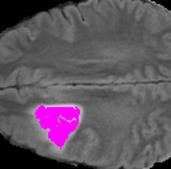

Weakly Supervised Semantic Segmentation (WSSS) relying only on image-level supervision is a promising approach to deal with the need for Segmentation networks, especially for generating a large number of pixel-wise masks in a given dataset. However, most state-of-the-art image-level WSSS techniques lack an understanding of the geometric features embedded in the images since the network cannot derive any object boundary information from just image-level labels. We define a boundary here as the line separating an object and its background, or two different objects. To address this drawback, we are proposing our novel ReFit framework, which deploys state-of-the-art class activation maps combined with various post-processing techniques in order to achieve fine-grained higher-accuracy segmentation masks. To achieve this, we investigate a state-of-the-art unsupervised segmentation network that can be used to construct a boundary map, which enables ReFit to predict object locations with sharper boundaries. By applying our method to WSSS predictions, we achieved up to 10% improvement over the current state-of-the-art WSSS methods for medical imaging. The framework is open-source, to ensure that our results are reproducible, and accessible online at https://github.com/bharathprabakaran/ReFit.